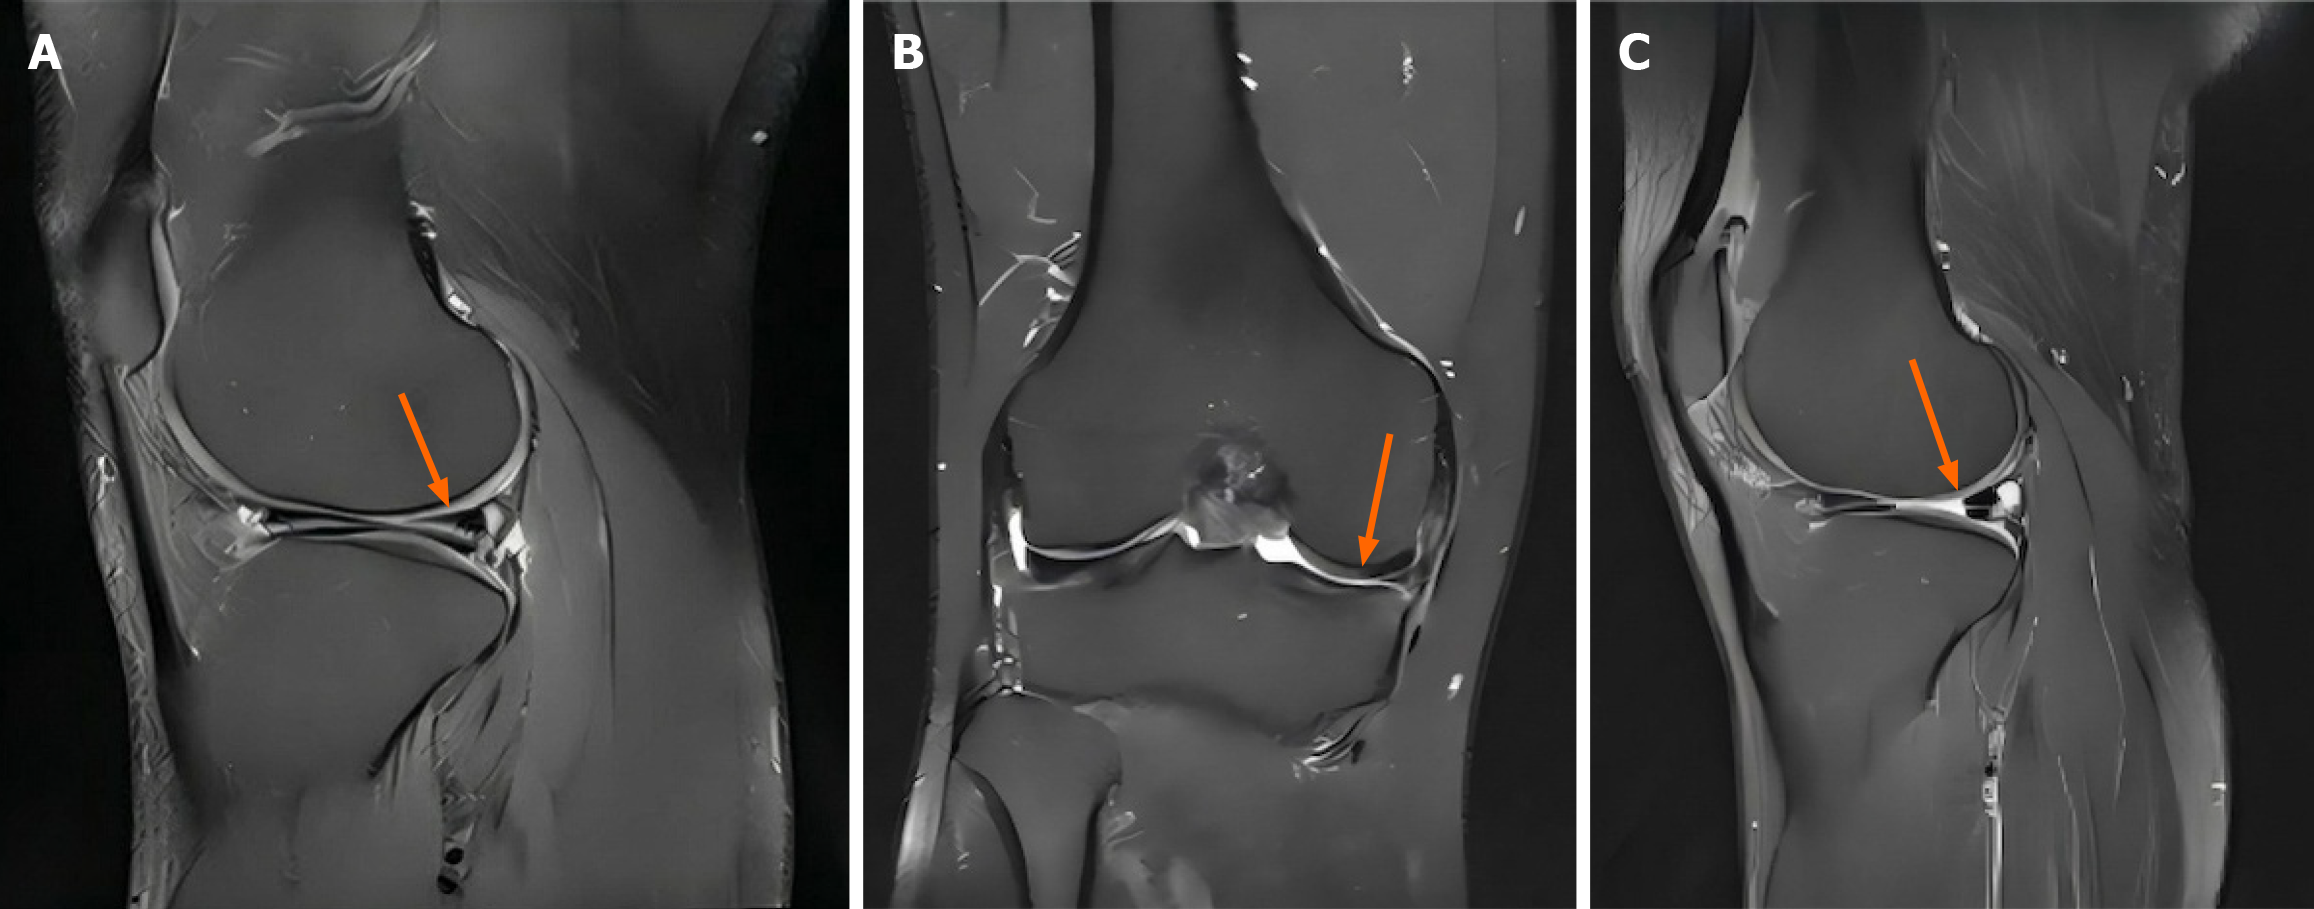

定量T2映射顯示,整個半月板平均T2弛豫時間從基線38.5±4.2毫秒降至6個月時的34.8±3.9毫秒和12個月時的31.2±3.8毫秒(均P<0.001),表明膠原結(jié)構(gòu)增強、水分含量降低(表2,圖2)。后角改善最為顯著(從41.2±5.1毫秒降至32.5±4.2毫秒)。形態(tài)學(xué)評估中,63.2%的患者半月板信號強度增強,40.8%的患者信號異常完全消退。最初存在的半月板擠出(平均3.8±1.2mm)在12個月時減少至2.9±1.0mm(P=0.003),其中35.3%的患者擠出量降至3mm以下。隨訪期間未見原有撕裂進展或新發(fā)撕裂。

A:治療前矢狀位T2加權(quán)像顯示內(nèi)側(cè)半月板后角高信號強度(箭頭),提示III級退行性改變;B:治療前冠狀位T2加權(quán)像顯示內(nèi)側(cè)半月板實質(zhì)內(nèi)信號異常(箭頭);C:治療后(12個月)矢狀位T2加權(quán)像顯示后角信號強度降低(箭頭)且組織均勻性改善。